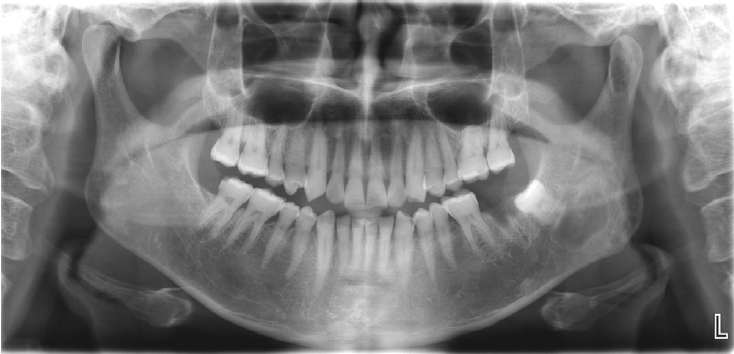

Histopathological analysis of the decalcified mandibular specimen revealed a mass predominantly composed of brown fat cells. Within the lesion, focal areas of cholesteatoma-like formation and numerous variably sized bony particle deposits were identified. Tumor cells exhibited eosinophilic granular cytoplasm with eccentric nuclei, consistent with adipocytic differentiation. Notably, the majority of the mass consisted of polygonal brown fat cells displaying multiple cytoplasmic vacuoles (Fig. 3). Based on the imaging appearance, the differential diagnosis favored non-ossifying fibroma, with simple bone cyst considered less likely. Intraosseous hibernoma was not initially suspected and was confirmed postoperatively by histopathologic examination. Overall, the findings supported a diagnosis of a lesion with extensive brown fat cells proliferation and secondary changes including bony particle deposition and cholesteatoma-like formation. These findings established the final diagnosis of intraosseous hibernoma. The patient has been followed periodically, and a 7-month postoperative panoramic radiograph and CBCT showed new bone formation along the superior, inferior, and lingual aspects of the postoperative defect consistent with healing, without evidence of recurrence (Fig. 4).

A. Panoramic radiograph at 7 months postoperatively shows new bone formation along the superior and inferior aspects of the postoperative defect, without recurrence. B. Cone-beam computed tomographic images at 7 months shows new bone formation along the superior, inferior, and lingual aspects of the postoperative defect.